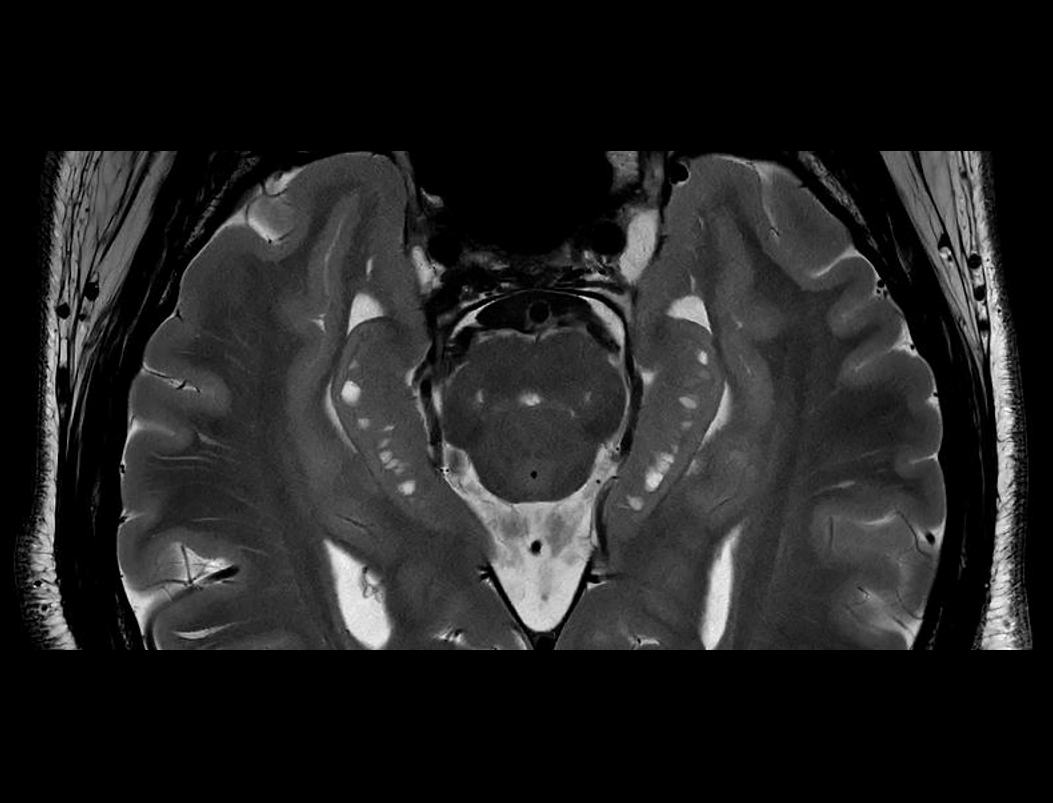

高分辨海马体 T2W